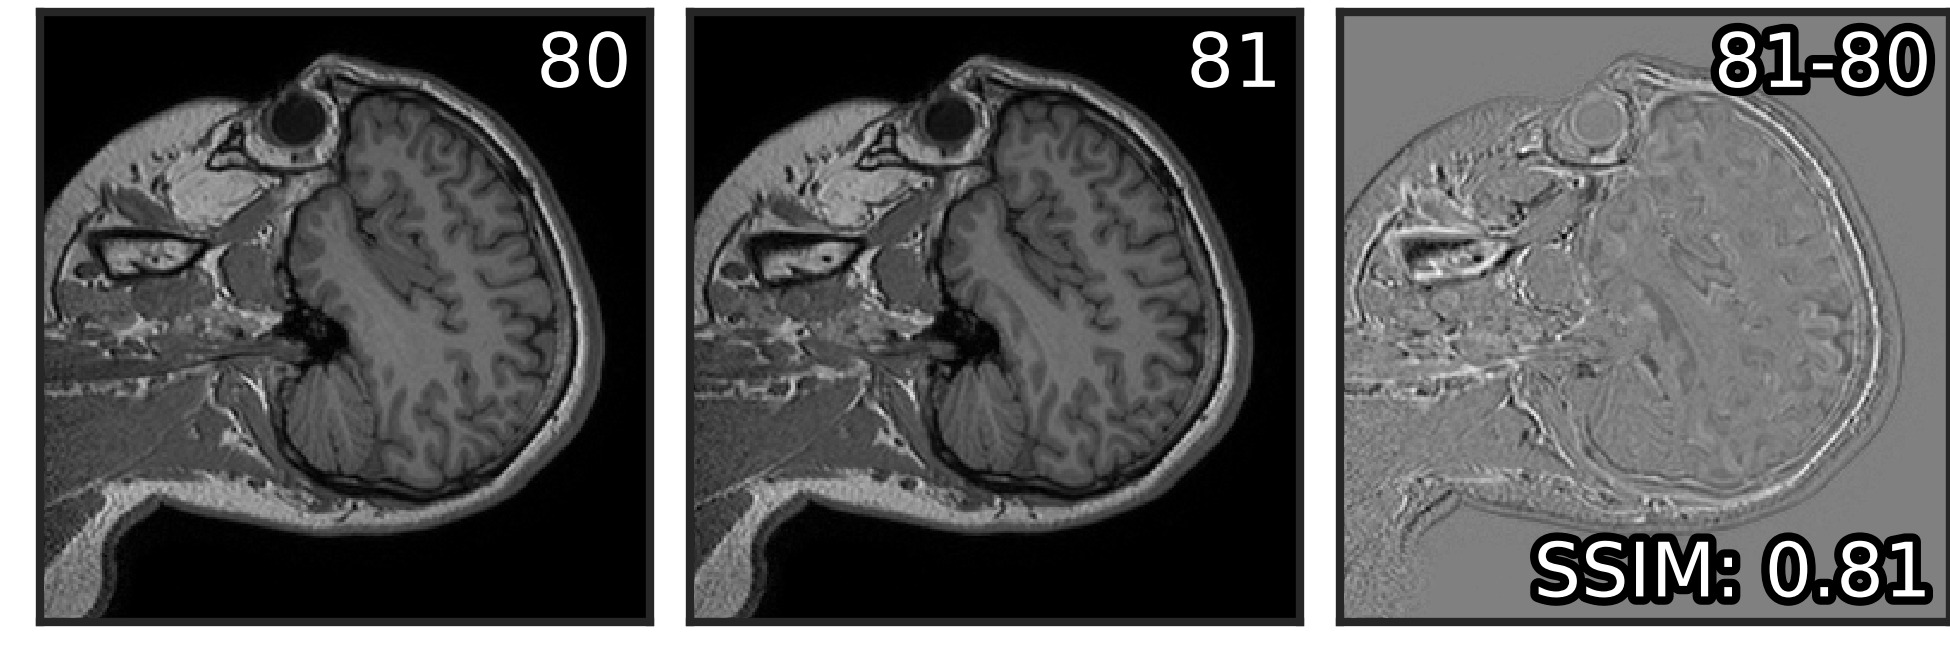

The Noise2Stack method was inspired by the observation of neighboring plane similarity in a number of volumetric biomedical datasets (Figure 1). For example, for MRI brain scan dataset that we used in our experiments (Section 2.2), the average structural similarity between neighboring planes is . We showed that U-Net is able to capture this mutual information and effectively use it for denoising. In both copy-supervised (where original Noise2Noise belongs) and self-supervised modes, two neighbors from each side (four total) were optimal for denoising of MRI. Two neighbors, one from each side, were best for the fluorescent microscopy. Adding more neighbors to the stack did not affect the performance in copy-supervised mode and made it slightly worse for self-supervised mode, where only neighbors were used as the network’s input. We hypothesize that this effect depends on the physical distance between imaged planes, and that the optimal number of planes differs between datasets. However, it is clear that further planes provide less useful information for the restoration and could lead to network overfitting.

Visually, the level of detail in MRI denoised with Noise2Stack in copy-supervised mode has noticeably increased comparing to Noise2Noise, as can be seen in Figure 3 (additional illustrations provided in Supplementary material, Figure S1). Brain gyri in the reconstructed images are clean and sharp even for the cerebellum where they are tiny. In self-supervised mode Noise2Stack results are expectedly less detailed and match Noise2Noise by sight. However, this mode demands twice less data, being able to learn from a single copy. For the fluorescent microscopy, Noise2Stack in self-supervised mode did not outperform supervised Noise2Clean, but has shown comparable results.